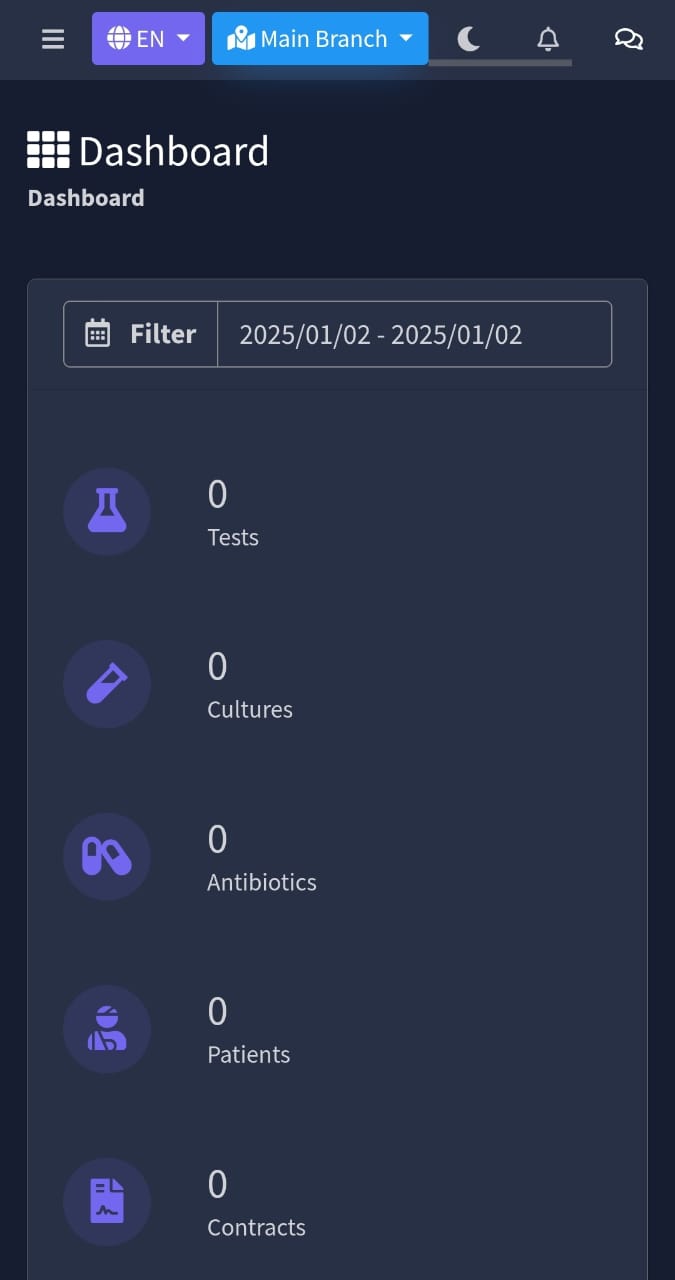

Perfect Responsive

Our Software & Website designs are fully Perfect for all device. You can use them on all device easily.